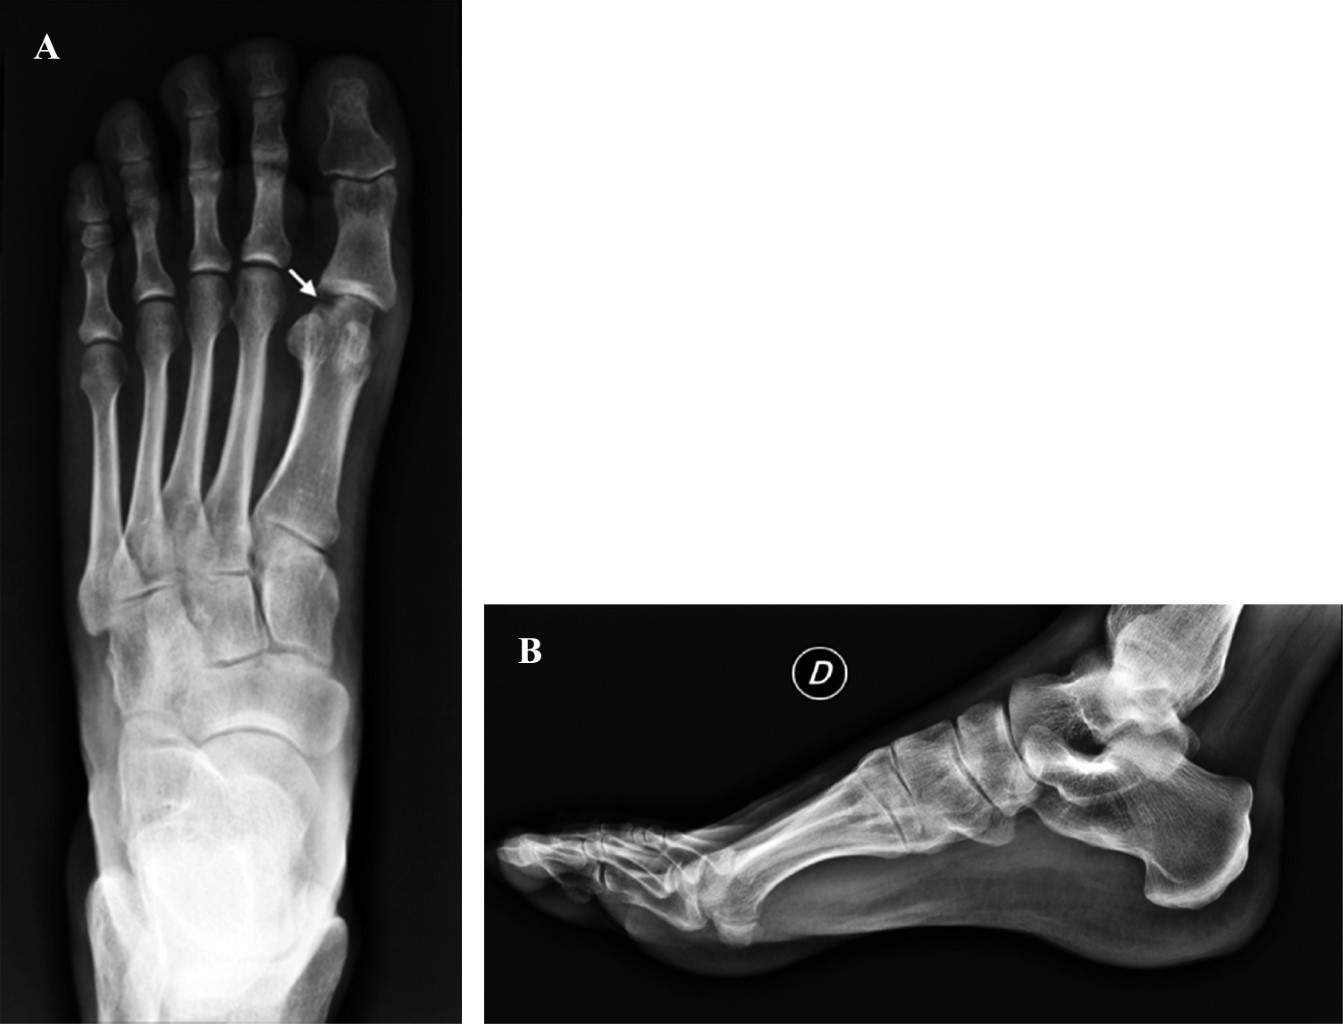

A los 1.7 años después de la cirugía, su rango de movimiento postoperatorio era de 60o de dorsiflexión activa y 40o de flexión plantar activa (Figura 4). El paciente negó dolor, malestar o debilidad en la articulación metatarsofalángica. Realizaba sus actividades de la vida diaria sin limitaciones y estaba satisfecho con los resultados postoperatorios.

Figura 3